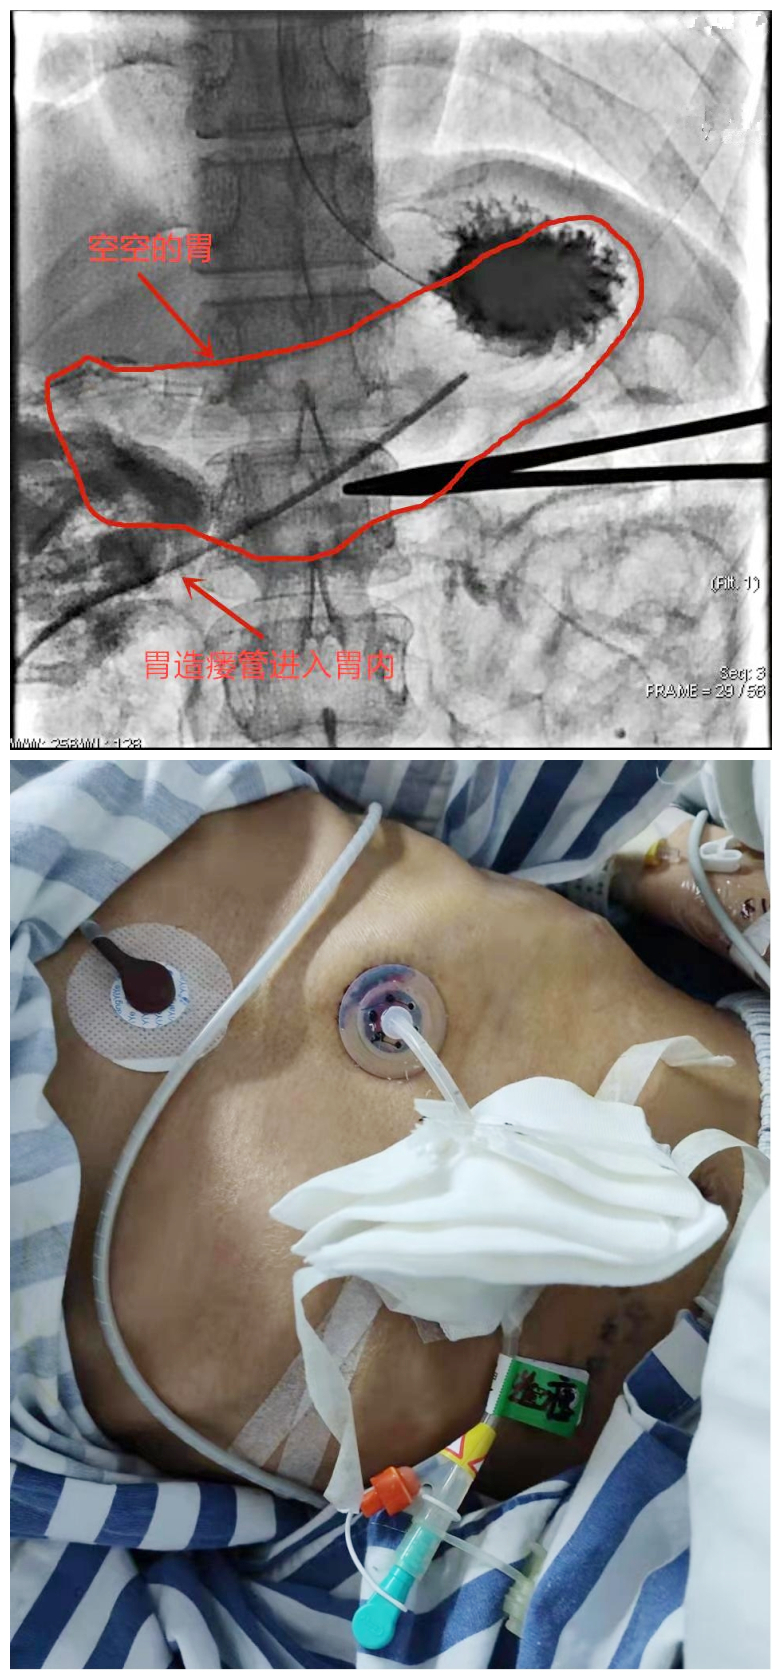

由于章先生身体虚弱,免疫能力低下,传统的鼻胃管会引起鼻咽不适,容易误吸食物导致肺部感染,危及生命。胃造瘘术则可减少上述情况的发生。胃造瘘术通俗的讲就是切开患者肚皮将喂养管放入胃内,食物可直接通过喂养管注入胃内,解决不能经口进食难题。但传统采用外科开腹胃造痿术创伤大、并发症多,对于极度虚弱的章先生来说手术风险很大。3月23日,在得知捷克论坛 马王堆院区介入血管外科可在局麻下行胃造瘘术,且只在腹壁上打个1厘米的小孔,能极大降低手术风险,患者来到马王堆院区求诊。因需要呼吸机治疗,患者先入住到急诊二部EICU病房。3月24日,在急诊二部和介入血管外三科医护人员的共同努力下,成功为患者行微创介入手术治疗。术后当天,患者就可以从胃造瘘管中注入糖水提供营养,术后第二天就可以注入流质食物。3月29日,经过几天术后康复治疗,章先生顺利出院了。

捷克论坛 急诊二部主任曹彦介绍,胃肠道不仅是消化吸收器官,更是重要的免疫器官,通过肠内途径进行营养支持,有助于维持肠黏膜结构和屏障功能完整性。实施微创胃造瘘术是给一些胃肠功能尚可,但因各种原因不能经口进食患者提供营养支撑的重要途径。微创胃造瘘术无需外科手术,相较于传统胃造瘘术具有经济实惠、安全快捷、并发症少等优点。(急诊二部  侯琨)